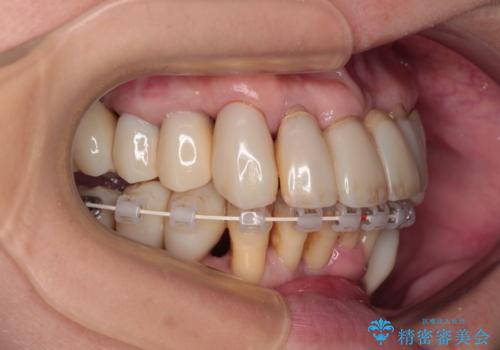

- 矯正装置

- 審美装置

歯周初期治療として抜歯や歯槽骨再生治療を行い、さらに歯周ポケット除去を行った後に矯正治療で歯列を整えて行くこととしました。

2~3年は早く終了する予定でしたが、途中で体調を崩されて来院されない時期が続いたため、非常に長期間の治療となりました。